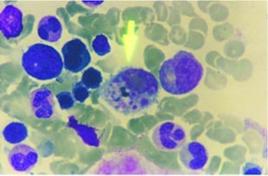

異常結果:漢坦病毒感染後2~3d,血清中可檢出lgM抗體,7~10d達到高峰,可作為早期診斷的指標;lgC抗體在感染後2周出現。